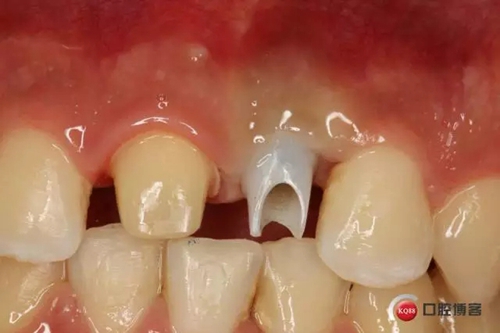

種植后修復(fù),我們要把握每一個細(xì)節(jié),比色,轉(zhuǎn)移桿的就位,我們必須把臨床做好,技工師傅才會給我們做出好的修復(fù)體,減少一些不必要的失誤,首先術(shù)前的檢查是必要一步 ,再是器械的準(zhǔn)備使我們臨床操作有條不紊,術(shù)前拍照,o-bite取咬合記錄,消毒修復(fù)術(shù)區(qū),旋出愈合基臺,生理鹽水沖洗袖口,拍照袖口,安放合適轉(zhuǎn)移桿,拍X線見轉(zhuǎn)移桿就為良好,硅橡膠取模,術(shù)后旋回愈合基臺,拍照比色。

藻酸鹽對頜取模,超硬石膏灌注。發(fā)加工廠,與技工溝通注意事項(xiàng),等修復(fù)體做好后,檢查模型。是否就位,是否密合,預(yù)約患者復(fù)診戴牙,消毒修復(fù)區(qū),旋出愈合基臺,定位器指導(dǎo)安放修復(fù)基臺,試戴冠,調(diào)磨鄰接及 咬合至合適,拋光,患者滿意,加力扳手加力至30N,拍X片見就位良好,特芙蓉及暫封膏封中央螺絲孔,聚羧酸鋅粘固劑粘固,或是樹脂水門汀粘固,清理多余粘結(jié)劑,光固化樹脂封螺絲孔,拋光。術(shù)后注意隨訪。